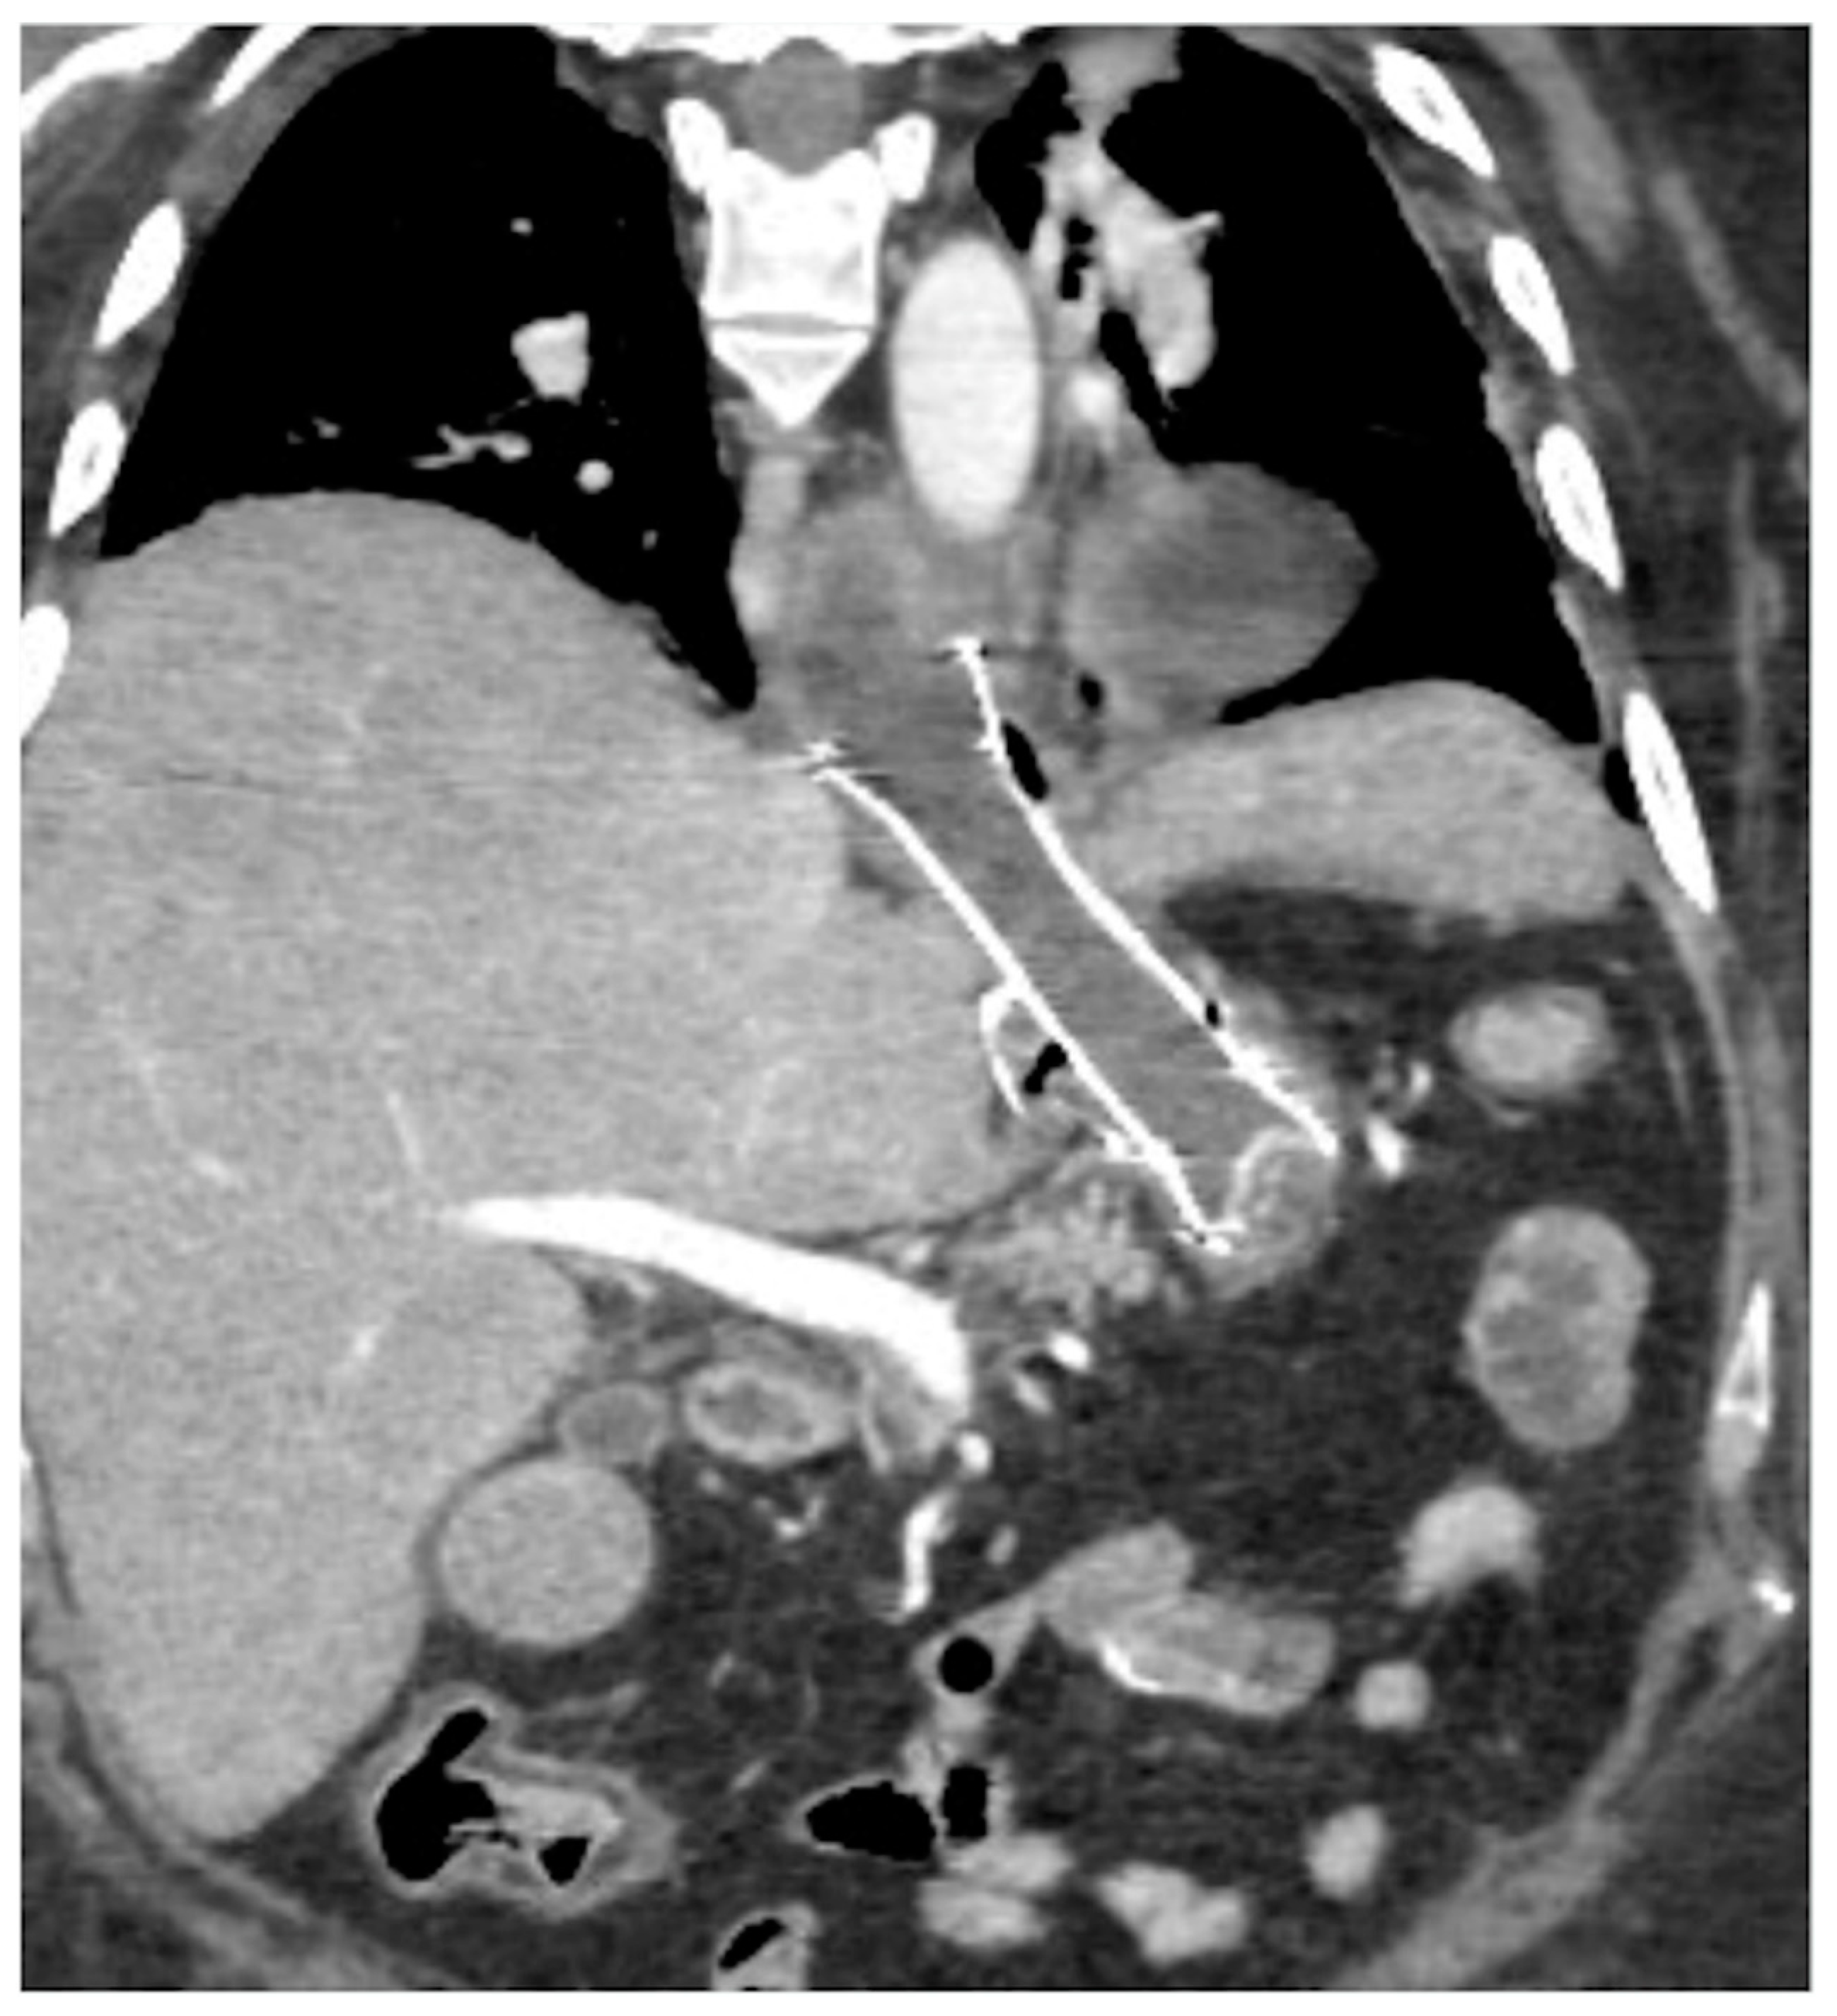

- Spleno-porto-mesenteric vein thrombosis (PVT)